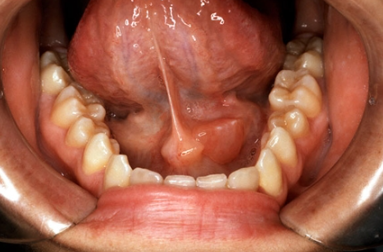

③ 타석증(침샘 결석)

침샘관 안에 돌(타석)이 생겨 침이 제대로 배출되지 않으면 반복적인 염증을 초래합니다. 타석 크기에 따라 저절로 배출되기도 하지만, 크거나 만성적인 경우 내시경적 제거 또는 수술이 필요할 수 있습니다.

다음 증상이 나타나는 경우에는 가급적 빠르게 이비인후과 또는 구강외과 전문의를 방문해 진료받는 것이 좋습니다.

의료기관에서는 영상 검사를 통해 침샘 상태를 확인하고, 필요한 경우 수술적 제거, 침샘내시경, 약물 치료 계획을 세웁니다.